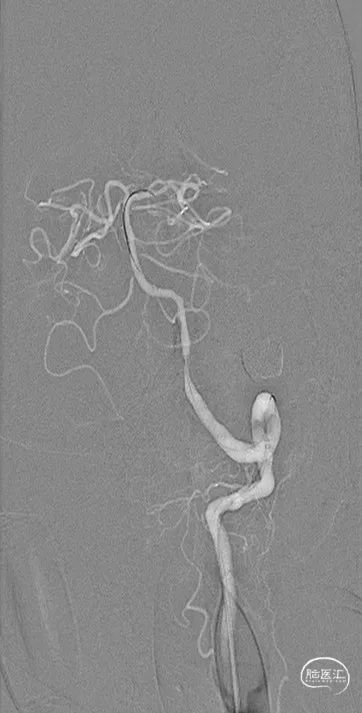

4.5mm*20mm自膨支架释放

复查造影

术后造影